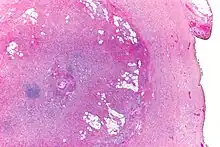

| Micrograph showing a goblet cell carcinoid. H&E stain. | |

Micrograph of a goblet cell carcinoid. H&E stain.

GCCs are diagnosed by pathology. They have a characteristic biphasic appearance which includes (1) goblet cell-like cells, and (2) neuroendocrine-type nuclear chromatin (stippled chromatin).